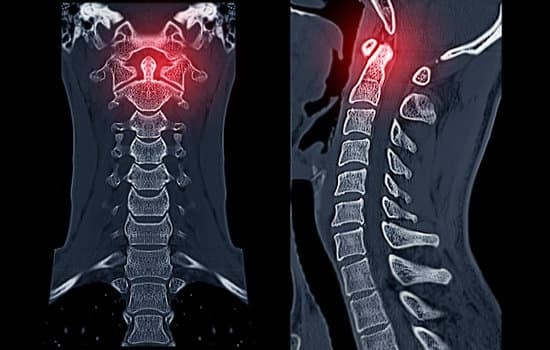

CT 스캔: 세부적인 뼈 손상을 확인할 수 있는 유용한 검사입니다.